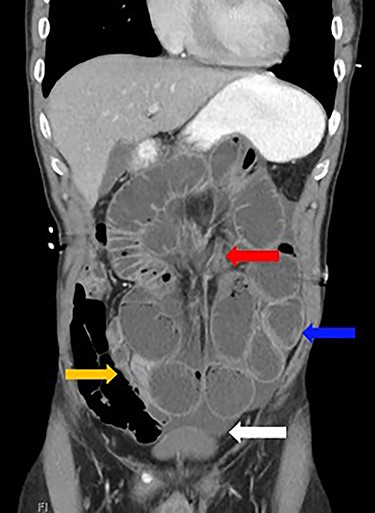

Dilated loops of small bowel (blue arrow), oedematous mesentery (suggestive of closed-loop obstruction; red arrow), free fluid (evidence of CA; white arrow) and collapsed small bowel (orange arrow)